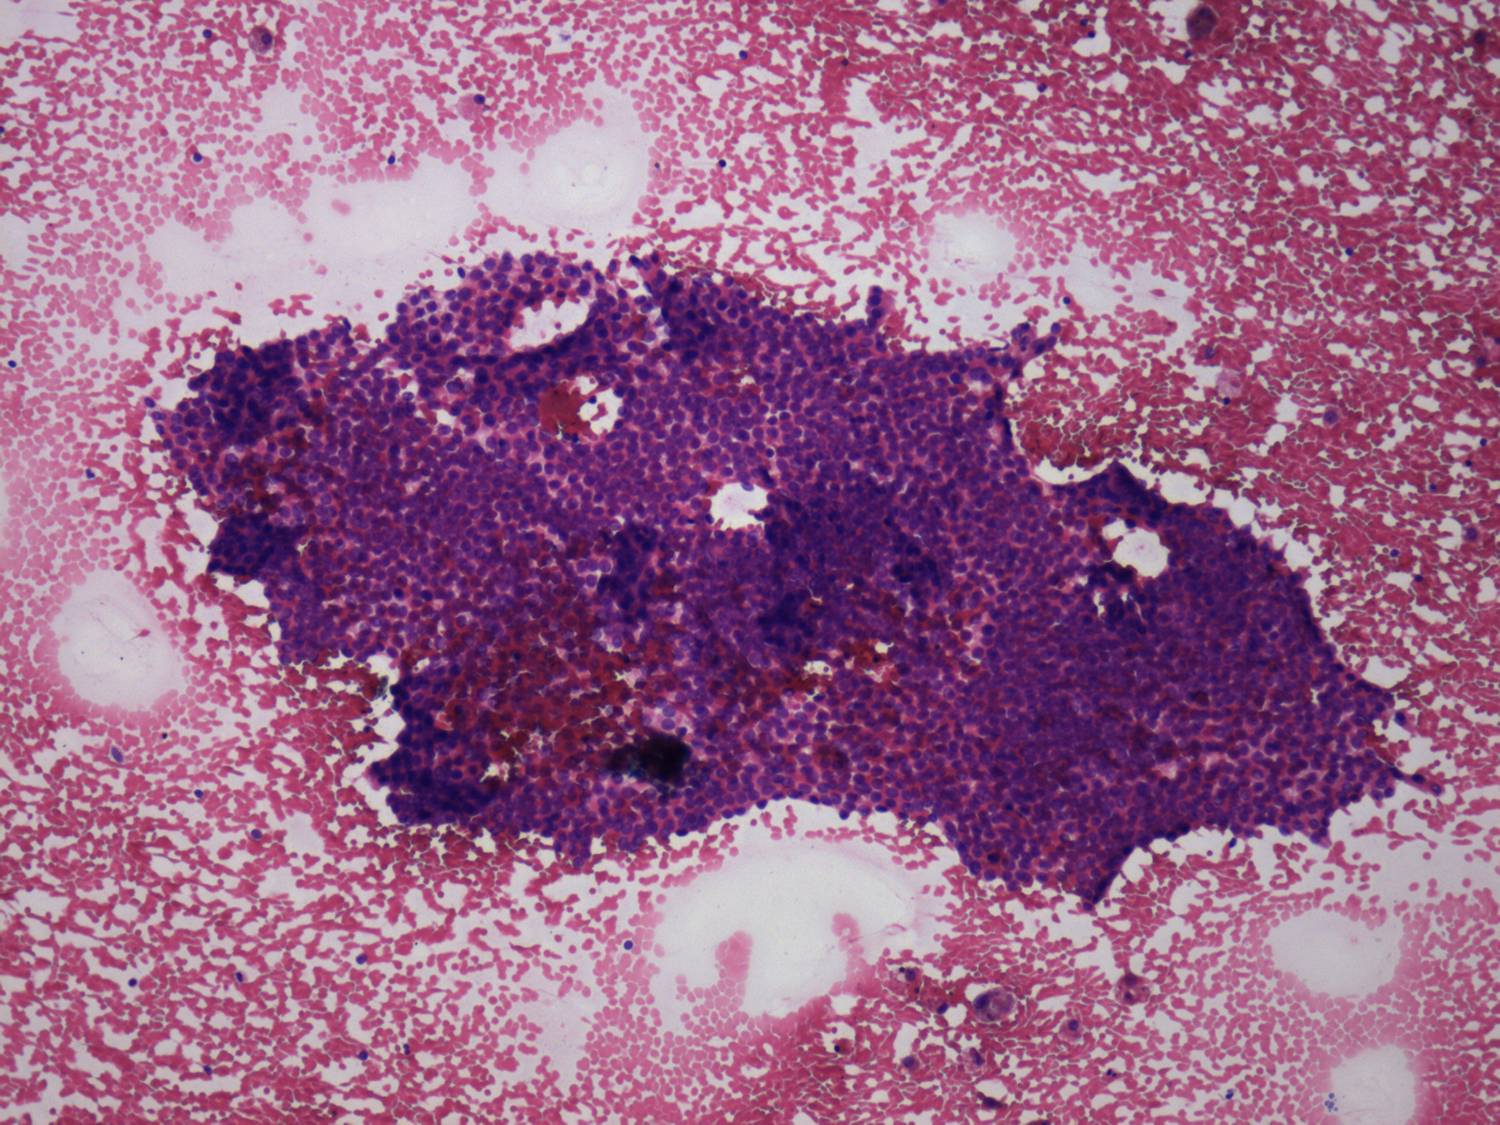

Cytological diagnosis: subacute, granulomatous de Quervain's thyroiditis.

Cytology from the cystic lesion in the right lobe resulted in papillary carcinoma.

Total thyroidectomy was performed. Histopathology discloses a papillary carcinoma. It was solitary with a 4 mm maximal diameter. The left lobe displayed no abnormality.